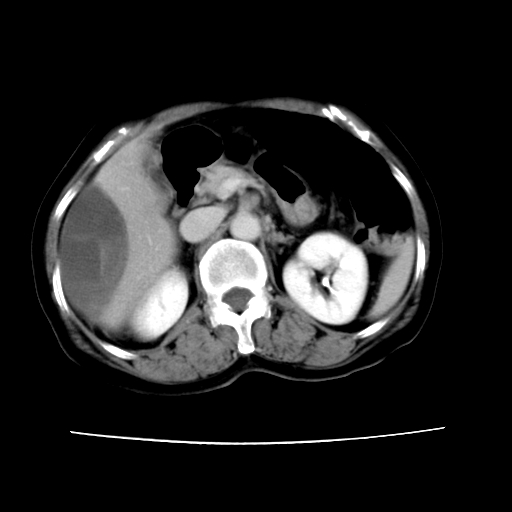

2008-11-10ct平扫(其间去中山医院诊治未行特殊治疗)

2008-11-10ct平扫见并肝内、血膜下血肿基本吸收,肝内低密度灶缩小。此时再做增强ct应有显着意义。对患者/医者都好!

从平扫+增强及治疗后复查片,病变明显缩小,不考虑肝癌出血可能,还是考虑为良性病变可能性大;单纯血肿并包膜下积液吧,病变强化没法解释,肝血管破裂出血吧,增强不符合典型血管瘤的表现,良性肿瘤破裂出血吧,复查片看来好像也不太支持(没做强化也不太好说)。本人还是考虑单纯肝内血肿并包膜下积液,强化是不是血管有外渗。

患者自6月至11月,如果是肝癌,没有经过特殊治疗,想必应该会有所进展吧,而不是ct所见,反而似有病灶减小的趋势。建议增强。

同意肝内肿块破裂致腹部疼痛,但不考虑肿瘤及血管瘤,增强不是血管瘤的特点,肿瘤半年时间内未经特殊治疗竟然快消失?考虑炎性改变或脓肿或寄生虫

病变破裂出血应首先考虑,病变性质即可能是恶性也可能是良性,楼主说患者到上级医院检查未见癌细胞,以良性可能性大,首先考虑腺瘤破裂出血可能。

追问病史,患者有过度用力病史,当时立即感腹痛;所以还考虑肝破裂可能性大。